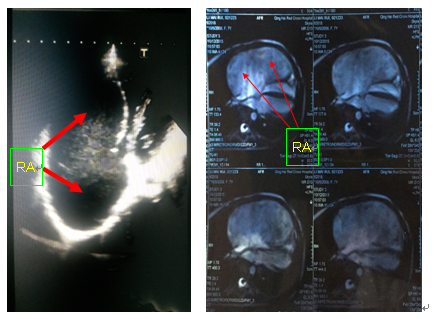

心脏超声及磁共振显示巨大的右心房(RA)